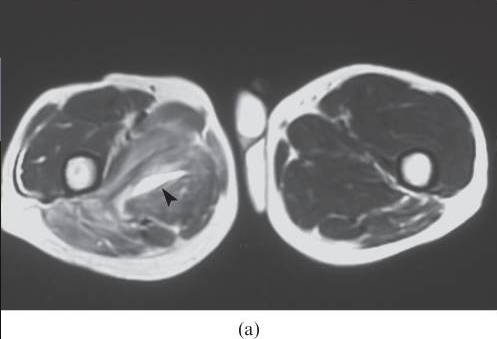

图23.骨化性肌炎在左四头肌肌肉组织中呈现为疼痛和可触及的肿块。 (a)轴向T1加权磁共振图像显示在股骨中间和邻近股骨近端的侧肌的明确边界的低信号强度区域(箭头)。 在臀大肌中观察到信号强度增加的另一个损伤(箭头)。 (b)相应的轴向T2加权的MR图像显示邻近近股骨(箭头)的低信号强度的成熟骨化病变,以及周围软组织(箭头)中的高信号强度包块。 观察到对应于水肿的异常高信号强度浸润臀大肌(星号)。 在切除时,发现臀大肌中的包块是未成熟的肌炎骨粘液,而成熟的骨从四头肌中的损伤中被检查到。